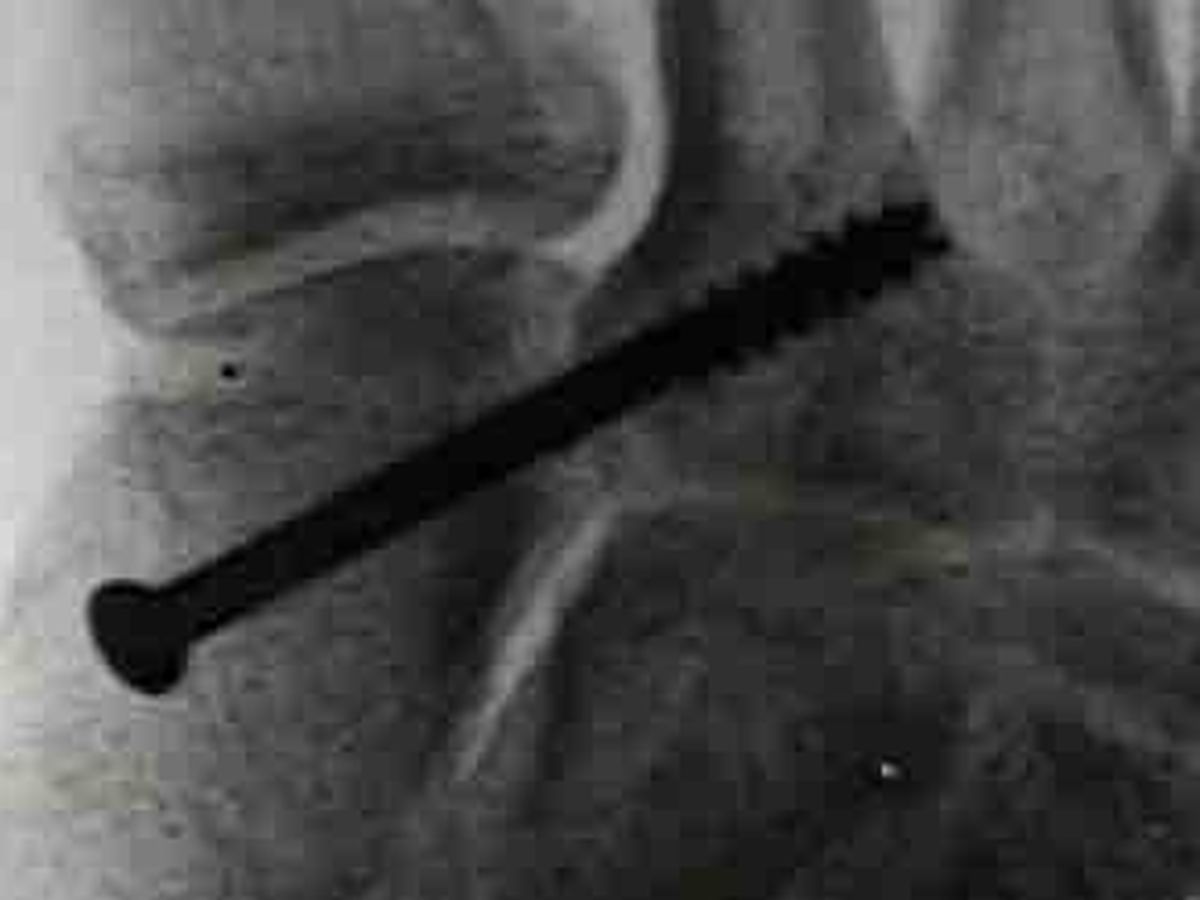

Result, fractures to the 2nd, 3rd, & 4th metatarsal bones in my right foot, overall foot/ankle sprains, and the worst, torn lisfranc joint which will require surgery to repair.